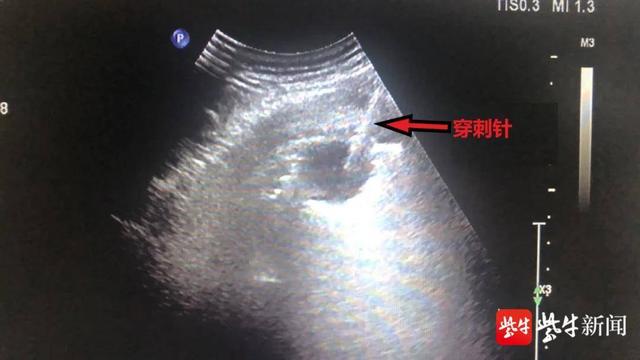

影像检查画面

超声引导下经皮肺穿刺活检术具有医患不接触射线、定位准确、方法简单、操作灵活、费用低廉、诊断准确率高等优点 , 并且能实时超声监视 , 显示肺脏周围的血管和脏器 , 可避开重要脏器及大血管 , 确保安全穿刺及取材的成功 。 对于贴近胸膜的肺部病灶 , 利用超声引导下经皮肺穿刺活检 , 成功率高 , 极少出现严重并发症 。